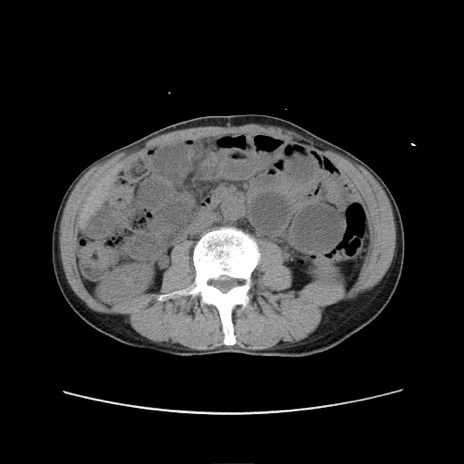

症例11(横断像)

【症例】 60歳代男性

【主訴】 下腹部痛

【現病歴】 本日夜中より下腹部痛の症状認め、受診。

【既往歴】 膀胱癌(膀胱全摘+尿管皮膚瘻術) 、胃癌術後

【身体所見】 BT 35.3℃、PR 58/min、BP 136/98mHg、腹部平坦、軟、腸蠕動音±、ストマ留置あり、左上腹部~正中部に圧痛あり、反跳痛なし。

【データ】WBC 5100、CRP0.01